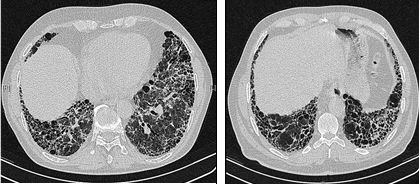

Idiopathische longfibrose: Hardnekkige obstakels

Al in 2017 werd in een parlementaire resolutie opgeroepen tot betere zorg voor idiopathische longfibrose (IPF), een zeldzame en ernstige ziekte. Acht jaar later staat het probleem opnieuw op de agenda.